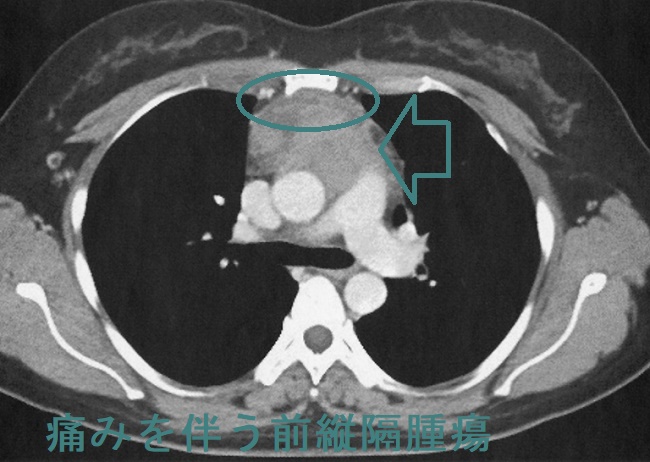

前縦隔に造影効果のある軟部濃度腫瘤を認め、胸腺腫瘍に特徴的な"へ"の字型形態です。

最も鑑別を要する胸腺腫はMRIで内部が不均一に描出される率が高いが、胸腺過形成は内部が均一に描出される(臨床放射線1995;40:825-30)

CTやMRIにおいて、①腫瘤内部に脂肪成分を含むため、まだら状の小結節性低吸収域が見られる、②MR脂肪抑制像(化学シフトMRイメージング)で正常胸腺と同じ生理的な脂肪成分が存在すれば胸腺過形成(Radiology2007;243:869-76)。

脂肪成分を含まない胸腺腫や胸腺癌(悪性胸腺腫、浸潤性胸腺腫)と鑑別されます。